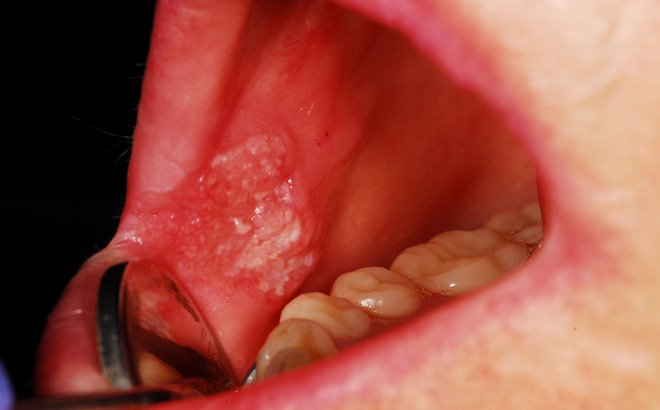

Các biểu hiện ung thư miệng giai đoạn đầu thường không rõ ràng và dễ nhầm lẫn với một số bệnh lý răng miệng thường gặp. Dưới đây, là một số dấu hiệu cảnh báo ung thư miệng mà chúng ta cần phải chú ý.